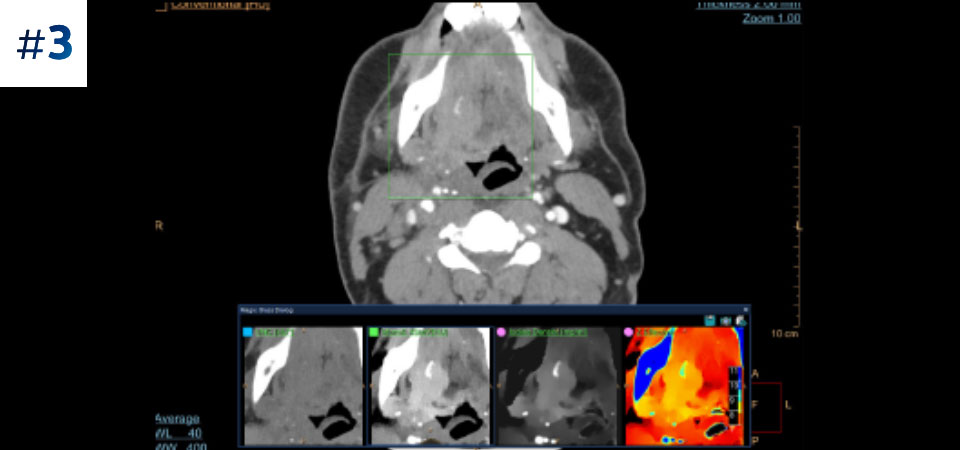

Neck mass

Go beyond conventional CT. See how layers of spectral-detector results can enhance your diagnostic confidence.